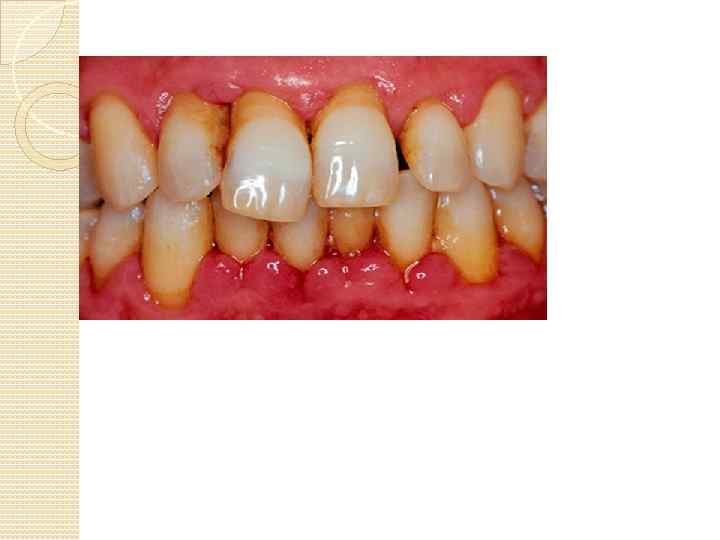

Гингивит-это воспаление десен, без нарушения целостности пародонта. Это начальная стадия развития болезней пародонта Ткань здоровых десен имеет светло-розовую окраску без каких-либо видимых вооруженным глазом изменений. Здоровая десна не кровоточит при правильной чистке зубов воспаленная ткань десен имеет темно-красную окраску и часто кровоточит при малейших прикосновениях к ней зубной щеткой. Если у Вас появилось ощущение, что Ваши зубы стали "длиннее", или их шейки обнажились (отхождение десны от зубов), это может свидетельствовать о начавшемся пародонтите. Наличие неприятного запаха изо рта. Причиной этого могут быть наличие назубных отложений, застрявшие в зубах, межзубных промежутках или в зубодесневых карманах. Покраснение, припухлость и напряжение десен. Веерообразное расхождение зубов, появление промежутков между ними. Появление гноя между зубом и десной при надавливании на десну.